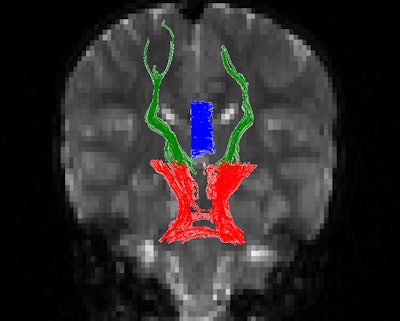

Diffusion-tensor MRI was performed on a 3-tesla scanner (Magnetom Trio, Skyra, or Verio, Siemens Healthcare) to assess white-matter tracts for the number of fiber trajectories, as well as tract volume and density, fractional anisotropy, and other measures.

The researchers found statistically significant differences in fractional anisotropy between the two groups, with the differences varying by three brain regions: the cerebellothalamic tracts, which are associated with working memory; the corpus callosum, which is associated with processing speed and IQ; and the thalamocortical tracts.

DTI fractional anisotropy measurements, chemo vs. no chemo | ||

Brain region | Chemo | No chemo |

Cerebellothalamic tracts | 0.484 ± 0.041 | 0.528 ± 0.048 |

Corpus callosum | 0.654 ± 0.037 | 0.703 ± 0.034 |

Thalamocortical tracts | 0.459 ± 0.049 | 0.469 ± 0.042 |